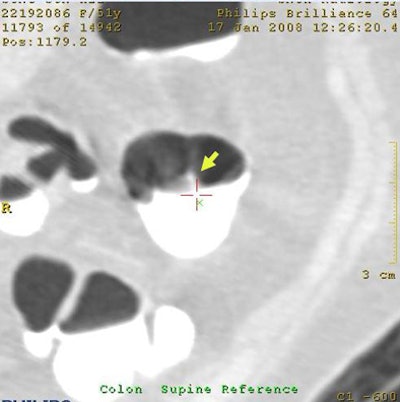

![]() |

| Without electronic cleansing, a 10-mm polyp was missed by CAD due to its flat morphology (top row above). After electronic cleansing was applied, CAD successfully detected this polyp (bottom row above). The lesion was confirmed as a well-differentiated adenocarcinoma on pathologic examination (below). |